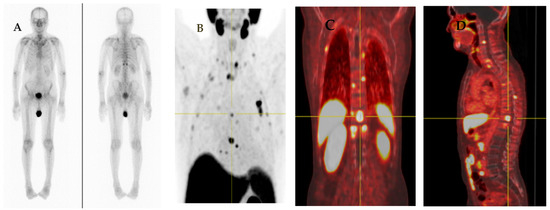

Figure 5.

A 75-year-old man with diagnosed PCa (Gleason score of 4 + 4, initial PSA of 43.12 ng/mL) who underwent 18F-PSMA PET/CT for initial staging. PET/CT scan reveals PSMA uptake at prostatic bed with multiple osteoblastic metastases at vertebrae. There are few subcentimeter mild PSMA-avid nodes at right lower paratracheal regions (SUVmax of 2.72) which are suspected of reactive nodes (A). Transaxial PET/CT in lung window (B) revealed increased PSMA uptake associated with reticulonodular infiltration at RUL which was suspected of pulmonary infection. After follow-up imaging, pulmonary lesion was improved, and mediastinal nodes revealed no significant change in size but no longer observable PSMA uptake.